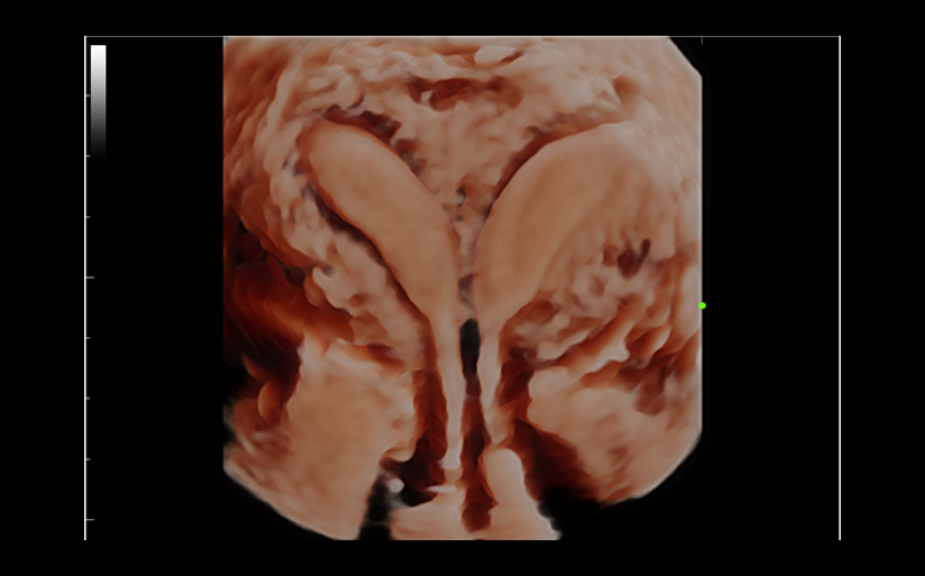

W aparacie DC-80A X-Insight zintegrowano inteligentne rozwi?zania z profesjonalnymi narz?dziami diagnostycznymi w ró?nych aplikacjach i podczas ca?ego cyklu badań: od pocz?tku ci??y, poprzez badania prenatalne, a? po opiek? poporodow?.

Obrazy kliniczne